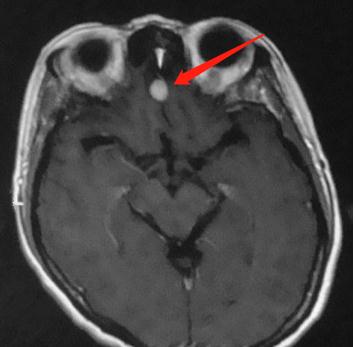

(3)嗅觉下降,出现幻嗅

有的脑膜瘤长在嗅沟,称为嗅沟脑膜瘤。我们的嗅神经从这里经过,这个地方如果长了脑膜瘤,就会压迫嗅神经,导致嗅觉下降。有的患者,还会出现幻嗅症状,也就是闻到本不存在的气味(类似于幻觉)

这是位于嗅沟的脑膜瘤